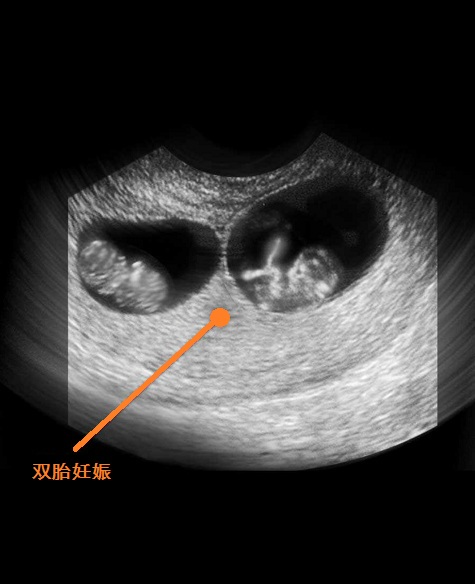

B超图

8周过去了,你的胚胎从现在开始可以称为“胎儿”了,也可以称之为“小宝宝”。为了接纳新居民,你的子宫膨胀得非常大,现在胎儿的尺寸大约有25毫米,而且胎儿许多位置都有所改变,如胚胎期的小尾巴不见了等。现在所有的器官、肌肉、神经开始工作。手部从手腕开始变得稍微有些弯曲,双脚开始摆脱蹼状的外表,眼帘开始覆盖住眼睛。